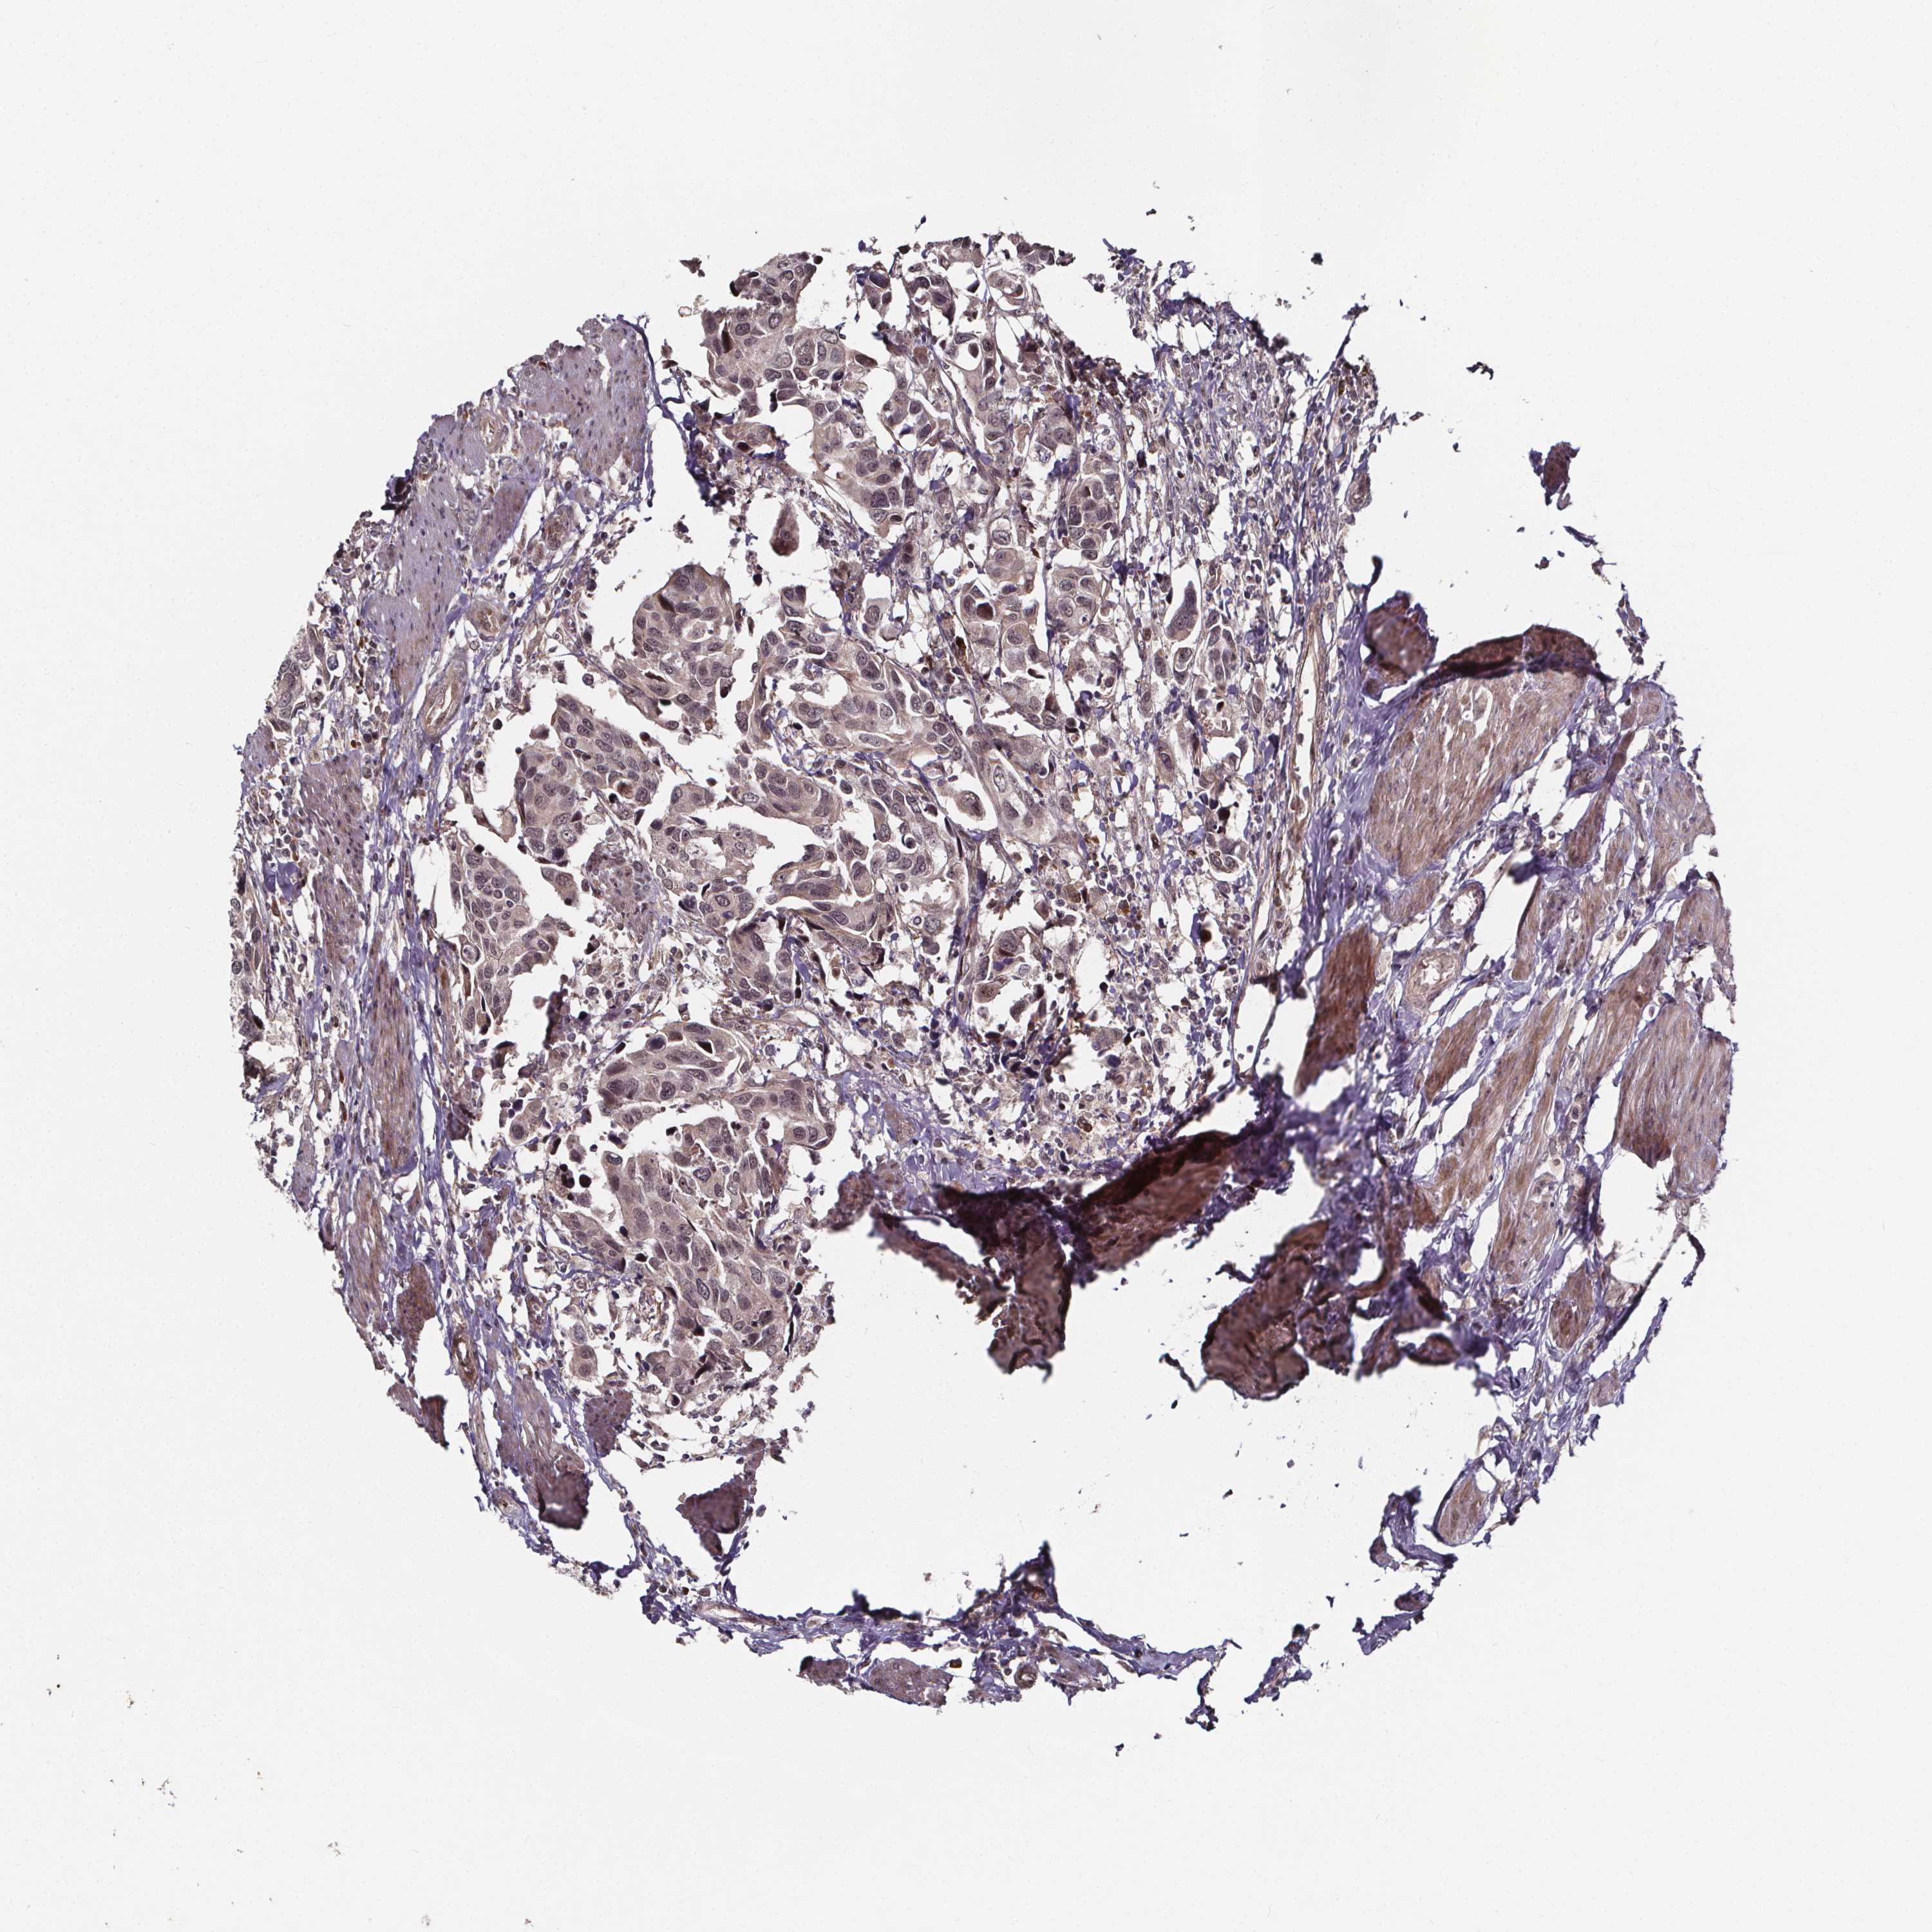

UROTHELIAL CANCER - Protein expressioni

A mouse-over function shows sample information and annotation data. Click on an image to view it in a full screen mode. Samples can be filtered based on level of antibody staining by selecting one or several of the following categories: high, medium, low and not detected. The assay and annotation is described here.

Note that samples used for immunohistochemistry by the Human Protein Atlas do not correspond to samples in the TCGA dataset.

Antibody stainingi

Antibody staining in the annotated cell types in the current human tissue is reported as not detected, low, medium, or high, based on conventional immunohistochemistry profiling in selected tissues. This score is based on the combination of the staining intensity and fraction of stained cells.

Each image is clickable and will lead to virtual microscopy that enables deeper exploration of all samples and also displays staining intensity scores, fraction scores and subcellular localization as well as patient and tissue information for each sample.

Antibody HPA068416

Staining

High

Medium

Low

Not detected

Intensity

Strong

Moderate

Weak

Negative

Quantity

>75%

75%-25%

<25%

None

Location

Nuclear

Cytoplasmic/membranous

Cytoplasmic/membranous,nuclear

Urothelial carcinoma, High grade

Urothelial carcinoma, NOS

Urothelial carcinoma, Low grade